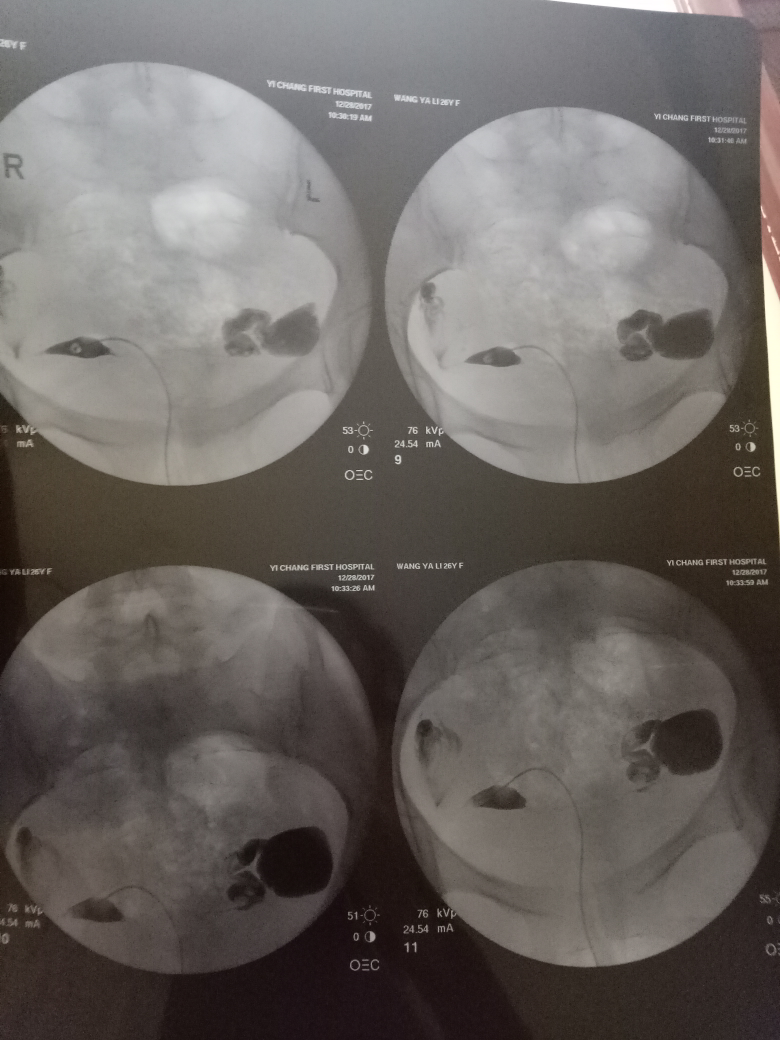

在現(xiàn)代醫(yī)學中,造影技術(shù)廣泛應用于臨床診斷,對于不孕癥的診斷和治療也起到了重要作用,造影是一種通過放射線、超聲波等影像技術(shù)觀察人體內(nèi)部結(jié)構(gòu)和狀況的方法,完成造影后的第二個月,很多夫婦關(guān)心是否容易懷孕,造影本身并不會直接影響懷孕,但了解身體情況后,有針對性地進行治療和調(diào)理,確實有助于提高懷孕的幾率。

通過造影技術(shù),醫(yī)生可以清晰地觀察到子宮內(nèi)部環(huán)境,如子宮內(nèi)膜厚度、輸卵管通暢情況等,若子宮環(huán)境良好,第二個月懷孕的機會將大大增加。

造影技術(shù)還可以評估卵巢功能,如卵泡數(shù)量、質(zhì)量等,若卵巢功能正常,有助于排卵和激素分泌,從而提高懷孕幾率。